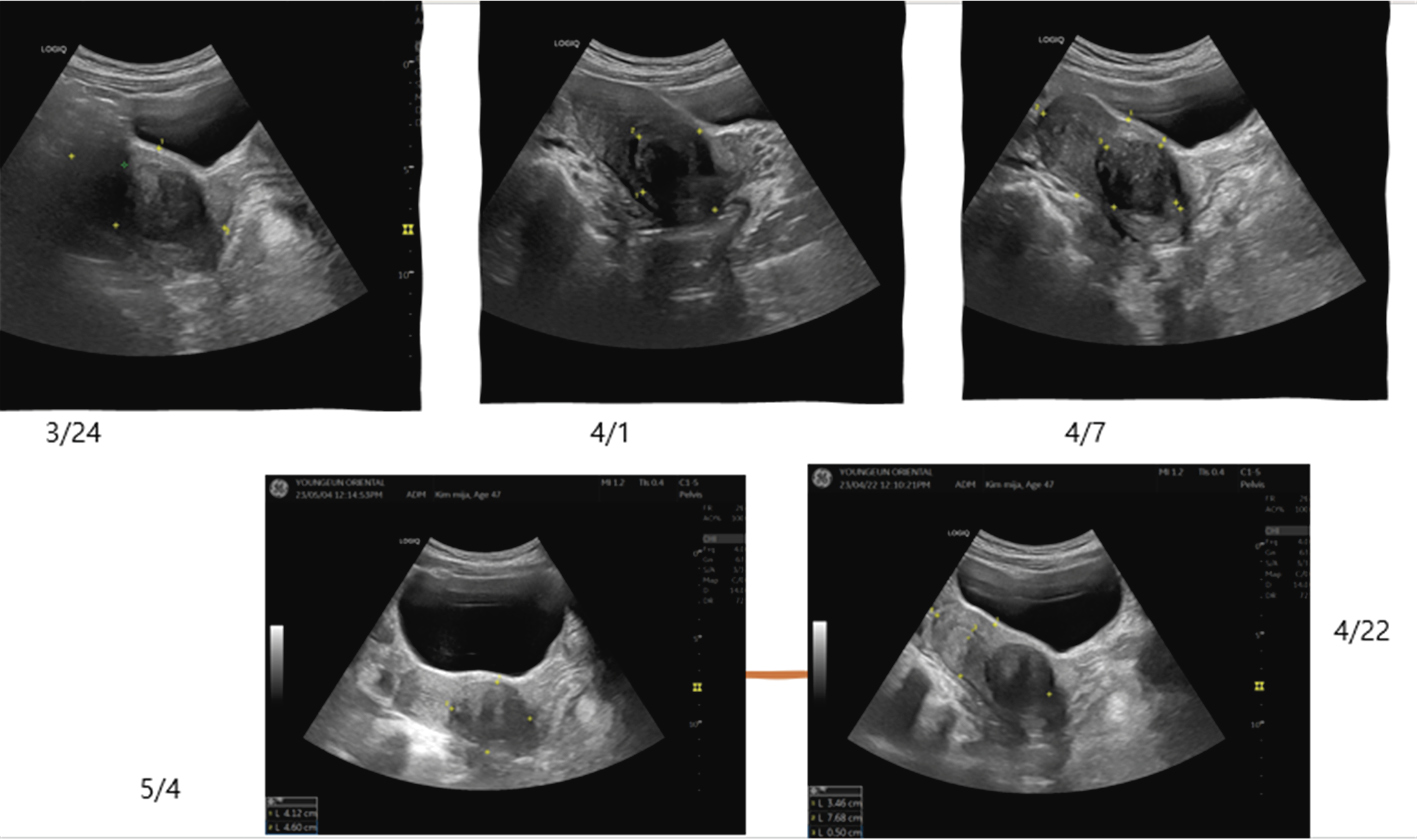

⑬ 3월24일. 맥 74/68 비(방광) 생리가 4일 뒤로 다가왔다. 초음파검사상 자궁경부에 4.74cm 자궁근종이 위치하고 있다. 크기 변동 없다. 녹각교‘

보통 목토형의 붕루에 가미귀비탕을 처방해야 하나, 이 환자는 설사를 자주하는 증상이 있어 동의보감의 설사문과 포문에 나오는 승양제습탕 중에서 포문의 승양제습탕가 녹용을 선방했다. 환자는 녹각교를 먹고 기력이 회복되고 하혈이 빠르게 멈췄지만 만성적인 소화불량과 설사로 빈혈이 심해 장기적인 치료가 필요하다고 사료된다. 초음파 사진상 상기 환자의 자궁경부쪽에 4.35cm의 자궁근종이 보인다. 자궁근종이 내막에 근접하면서 붕루증상을 일으킨 것으로 보인다. 치료 중 초음파로 관찰한 결과 자궁내막 근처 정상조직이 성장하면서 자궁근종으로 눌리면서 하혈하는 증상이 개선되고 있었다.